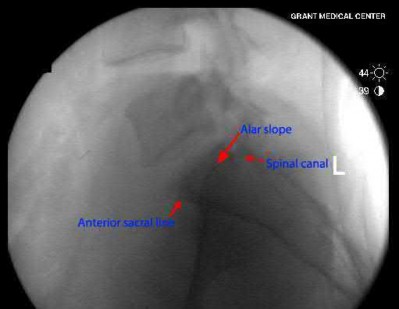

Which of the following images shows an injury pattern most consistent with a lateral compression type 3 pelvic ring injury?

Figure C is an axial CT scan of a lateral compression type 3 (LC3) pelvic ring injury.

Classically, LC3 injuries demonstrate an ipsilateral lateral compression and a contralateral APC (windswept pelvis) fracture pattern. The most common mechanism of injury in these cases is a rollover MVC or pedestrian vs. auto. LC1 injuries are characterized by an oblique or transverse ramus fracture and ipsilateral anterior sacral ala compression fracture, while LC2 injuries consist of a rami fracture and ipsilateral posterior ilium fracture dislocation (crescent fracture). While LC1 injuries can often initially be managed conservatively with protected weight-bearing and close observation, LC2 and LC3 pelvic ring injuries are almost universally operative.

Pennal et al. discuss a radiologic technique for assessing the forces producing pelvic disruption and its use in logically classifying pelvic injury. Based on this radiologic assessment and along with some biomechanical studies, they propose a classification system involving three major forces producing injury that can also be helpful in the management of these patients.

Young et al. performed a retrospective analysis of the plain radiographs of 142 cases of pelvic fractures and identified four patterns of force that presented with distinctive, recognizable radiographic appearances. They describe a classification system for pelvic fractures based on radiographic and clinical findings that correlates with associated injury to soft-tissue structures and enables the surgeon to begin corrective procedures rapidly.

Incorrect Answers:

Answer 1: This represents a lateral compression type 2 injury. Answer 2: This represents a lateral compression type 1 injury.

Answer 4: This represents an anterior posterior compression type 2 injury. Answer 5: This represents an anterior posterior compression type 3 injury.